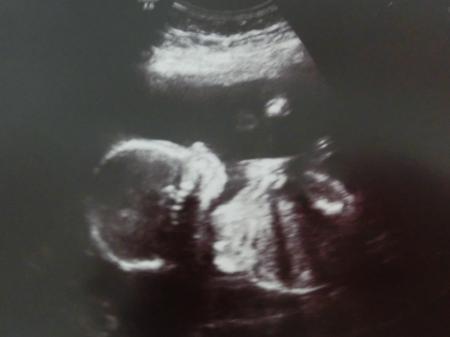

Oooh das zweite Bild gefällt mir sehr gut :) ich mag diese Bilder so gerne